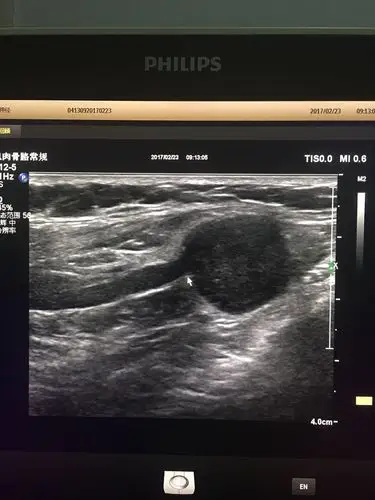

乳腺纤维瘤? - 超声医学讨论版 - 爱爱医医学论坛